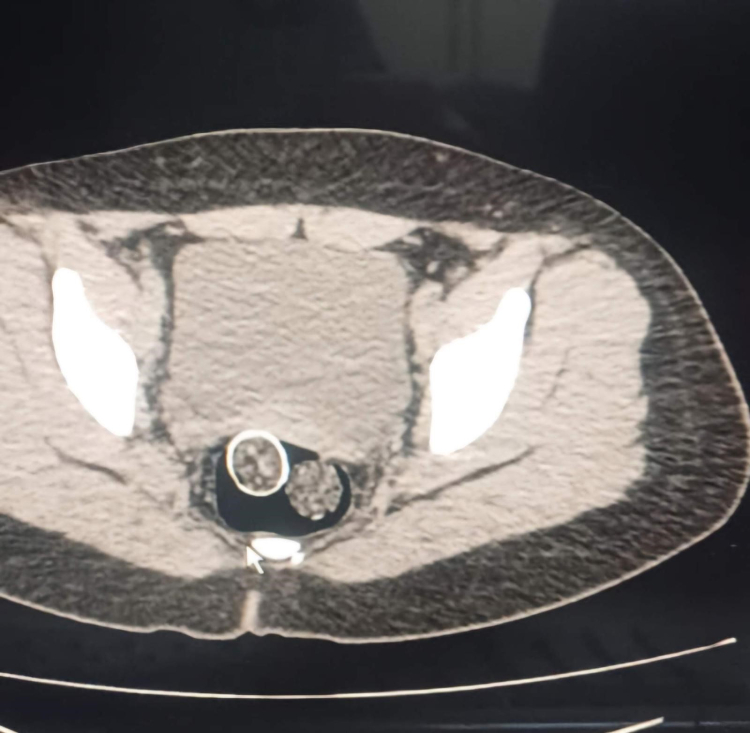

Denizli İl Emniyet Müdürlüğü Narkotik Suçlarla Mücadele Şube Müdürlüğü ekiplerince, uyuşturucu ticaret yapan şahıs veya organizasyonların yakalanmasına yönelik operasyon düzenlendi. Düzenlenen eş zamanlı operasyonlarda 5 şüpheli şahıs yakalanırken, iki şahsın yaptırılan iç beden muayenesinde ve kullandıkları iki araçta yapılan incelemelerde rahimde ve midede uyuşturucu madde tespit edildi.

Operasyonda 6 parça halinde 320 gram metamfetamin maddesi, 1,6 gram afyon sakızı maddesi, uyuşturucu madde ticaretinden elde edildiği değerlendirilen 114 bin 430 TL, 12 bin 595 Euro, 300 dolar, 1 adet sahte pasaport ele geçirildi. Ayrıca yakalanan şüpheli şahıslardan 1 şahsın 6 yıl 8 ay kesinleşmiş hapis cezası ve 16 bin 600 TL adli cezası ile arandığı tespit edildi.